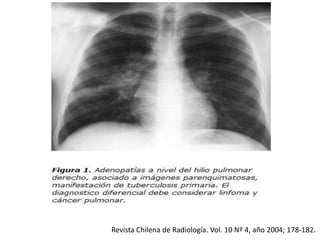

Figura 2: Las opacidades parenquimatosas pueden ser tanto del espacio

aéreo como del intersticio, siendo la consolidación del espacio aéreo el

patrón radiológico más común